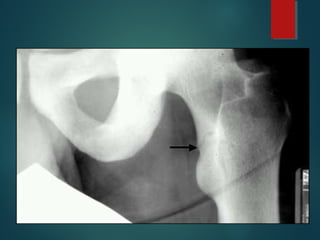

OSTEONECROSIS cont…..

Morphology:

Pathological features are the same with all causes

 Medullary infarct

- The necrosis is spotty involve cancellous bone and

marrow.

- Cortex not affected

 In subchondral infarcts

- A triangular wedge-shaped necrosis

- overlying articular cartilage not affected.

Note the wedge-shaped area of avascular necrosis

(osteonecrosis) at the upper right of this femoral head.

Avascular necrosis results from bone ischemia, which

can be due to many causes, including trauma and

corticosteroid administration, though idiopathic cases

are common. There is pain with activity, progressing to

pain at rest. Eventually, the necrotic bone collapses,

distorting the overlying articular cartilage and

OSTEONECROSIS

OSTEONECROSIS cont….. Morphology: Pathological featuresare the same with all causes  Medullary infarct - The necrosis is spotty involve cancellous bone and marrow. - Cortex not affected  In subchondral infarcts - A triangular wedge-shaped necrosis - overlying articular cartilage not affected.

• 85.

Note the wedge-shapedarea of avascular necrosis (osteonecrosis) at the upper right of this femoral head. Avascular necrosis results from bone ischemia, which can be due to many causes, including trauma and corticosteroid administration, though idiopathic cases are common. There is pain with activity, progressing to pain at rest. Eventually, the necrotic bone collapses, distorting the overlying articular cartilage and